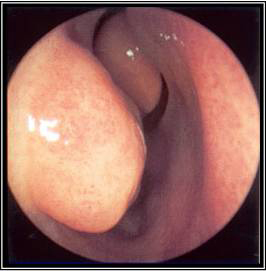

აუცილებელია ცხვირის ღრუს შემოწმება ლორწოვანი გარსის ერითემის ან ჩირქოვანი გამონადენის არსებობაზე. ოპტიმალური შემოწმების ჩატარება შესაძლებელია შეშუპების საწინააღმდეგო სპრეის ლოკალური დატანების შემდეგ.[17] როგორც ოტოსკოპი, ისე ნაზალური სარკე და რეფლექტორული განათება შეიძლება იყოს გამოყენებული. ცალმხრივი ჩირქოვანი გამონადენი, ლორწოვანი გარსის შეშუპება ან ერითემა, აგრეთვე სახის არეში მტკივნეულობა მიანიშნებს ბაქტერიული სინუსიტის არსებობაზე. არაჩირქოვანი გამონადენი საფიქრებელს ხდის ვირუსული ან ალერგიული ანთების არსებობას. იმის გათვალისწინებით, რომ ნაზალური გასინჯვა შესაძლოა იყოს გაძნელებული, ან ავლენდეს მხოლოდ არა-სპეციფიურ ნიშნებს, ცალკეული პაციენტებისთვის რეკომენდებულია ნაზალური ენდოსკოპიის ჩატარება, კერძოდ, ემპირიული ანტიბიოტიკოთერაპიის მიმართ რეფრაქტერული პაციენტებისთვის, როდესაც არსებობს ეჭვი ანტიბიოტიკებისადმი რეზისტენტობაზე, ან პაციენტი არის იმუნოკომპრომენტირებული.

ენდოსკოპია იძლევა ცხვირის ღრუს და სინუსების სადრენაჟე გზების საუკეთესო ვიზუალიზაციის საშუალებას. არსებობს ორი ტიპის ენდოსკოპი: რიგიდული და ელასტიური. რიგიდულ ნაზალურ ენდოსკოპს უკეთესი რეზოლუცია გააჩნია და მისი მართვა ცალი ხელით შეიძლება. ეს აადვილებს საჭიროების შემთხვევაში კულტურების მიღებას ცხვირის ღრუდან ან წიაღიდან. ელასტიური ნაზალური ენდოსკოპი პაციენტებისთვის უფრო კომფორტულია, მაგრამ მისი მართვა ორივე ხელის დახმარებით ხდება. არსებობს დრეკადი ცხვირის ენდოსკოპი, რომელსაც აქვს კულტურის შეგროვების არხი, მაგრამ უფრო დიდი და არასასიამოვნოა და მათი დამუშავებაც უფრო რთულია. ზოგადად, დრეკადი ენდოსკოპის გამოყენება უმჯობესია ბავშვთა ასაკში მისი კარგი ამტანობის გამო; თუმცა როგორც მოზრდილების, ისე ბავშვთა გამოსაკვლევად შესაძლებელია ორივე ტიპის ენდოსკოპის გამოყენება. არჩევანი დამოკიდებულია შემსრულებლიექიმის გამოცდილებაზე და შემთხვევათა უმეტესობაში იშეიძლება ჩაატაროს ყელ-ყურ-ცხვირის სპეციალისტმა.

პერი-ორბიტალური ან ყვრიმალის არის შეშუპების, ორბიტალური პროფტოზის, მხედველობის დარღვევების, პათოლოგიური ექსტრა-ოკულარული მოძრაობების, ან პათოლოგიური ნევროლოგიური ნიშნების არსებობა შესაძლოა მიანიშნებდეს გართულებების არსებობაზე, როდესაც აუცილებელი ხდება ოტოლარინგოლოგის გადაუდებელი კონსულტაცია.[Figure caption and citation for the preceding image starts]: მარჯვენა ქვედა ნიჟარა და ძგიდე ხილვადია შეშუპების საწინააღმდეგო სპრეის დატანებამდე.ექ. Melissa Pynnonen-ის კოლექციიდან [Citation ends].